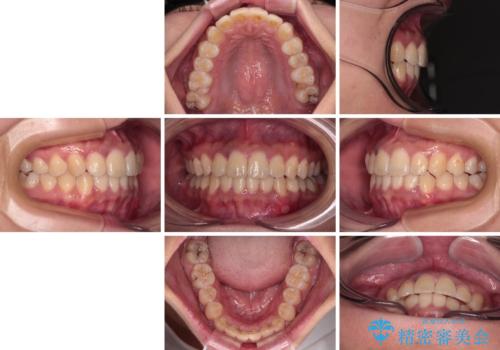

前歯のデコボコと隠れてしまう下顎前歯 インビザラインですっきりと改善

- 前歯のデコボコと、深い咬み合わせにより前歯が隠れていることを気にして来院された患者様です。

海外に長期滞在する予定があるとのことで、インビザラインにて矯正治療を行うこととしました。

インビザライン発注後に長期滞在先から2年間ほど帰国することができず、インビザラインの有効期限内に終了できるのか不安でしたが、矯正治療開始後は十分な装着時間を達成され、1年未満の期間で無事に終えることができました。